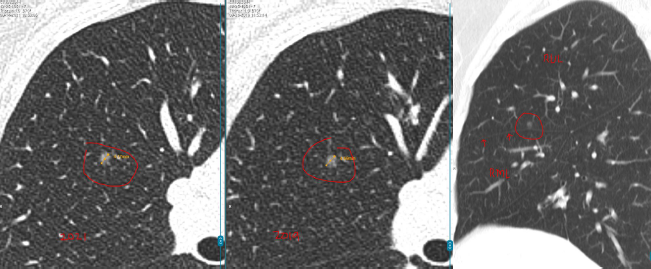

数年前,孙女士(化名)在一次体检中意外查出双肺多发结节:

- 左肺下叶:2枚实性结节,约5mm、3mm

- 右肺上叶:1枚磨玻璃结节,约4mm

每年复查,她都紧张得睡不着。好在3个结节都一直很“老实”,没变大。可四年后的一次CT复查,让她的心又提了起来:

左肺结节无变化,但右肺的4mm结节密度增高了,还又新添了一颗3mm的磨玻璃结节。

L教授详细查看了孙女士4年来的全部影像资料后,给出的结论让她长舒了一口气。

教授指出,右肺那颗4mm的磨玻璃结节虽然密度略有增加,但变化非常小,还不足以判断为恶化。

而左肺的两枚实性结节稳定了三年多,良性可能性超过99%。另外舌叶可见线状影,较前稳定,符合炎性、瘢痕特征。

至于新出现的那颗3mm磨玻璃结节,教授认为它也很“温和”,更像是一种暂时的炎性反应,有可能过段时间就自行消失了。